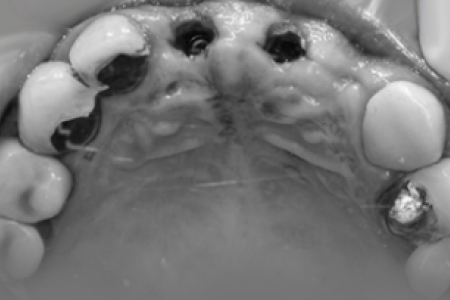

가이드 장착 후 수술

제작한 네비게이션 가이드를 수술 전 구강에 장착한 뒤 계획한 위치에 정확하게 수술합니다.

계획한 위치에 식립

모의수술로 계획한 위치에 정확하게 임플란트가 식립됩니다. 내 치아같은 보철물로 자연스럽게 제작됩니다.